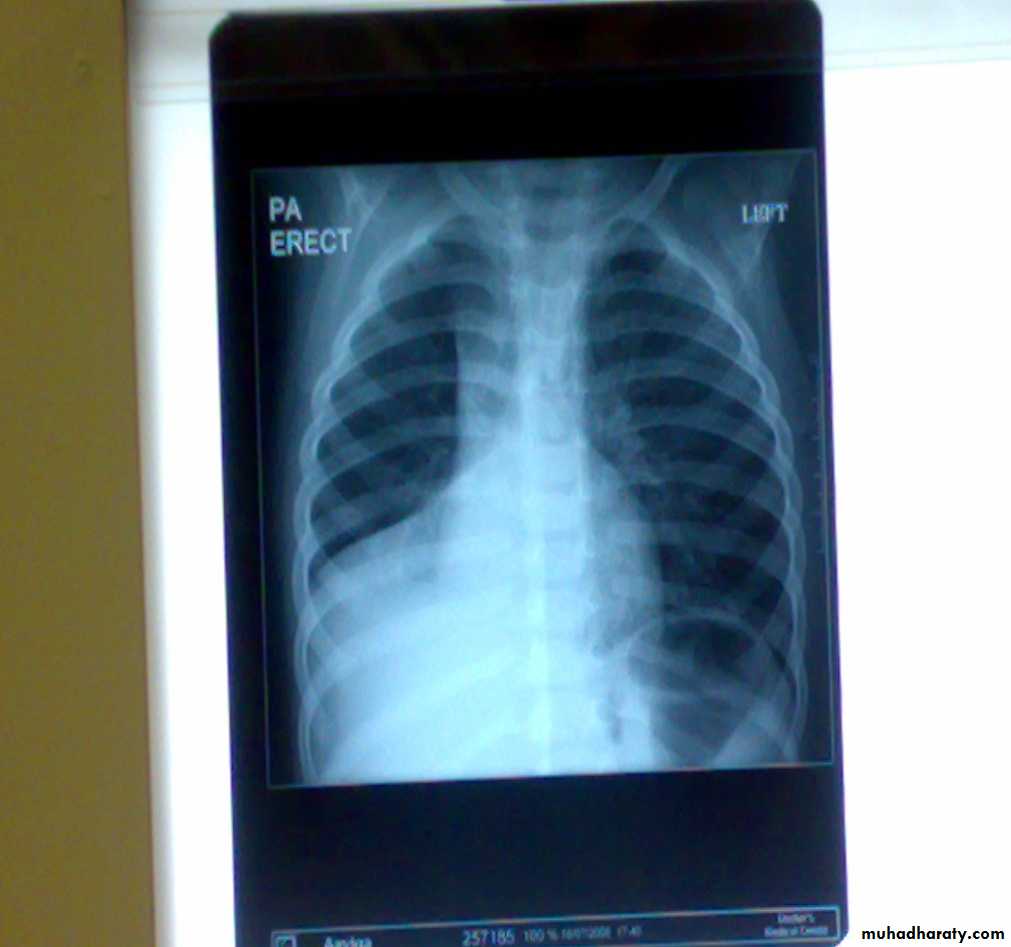

• 1-Spontaneous pneumothorax

Is the accumulation of air inside the pleural cavity , occurring without any known etiology .More in males ,more on the right side .It can be bilateral

• Causes 1- Ruptured pulmonary bleb.2-Ruptured of a cystic defect in the pleura.3-Teared visceral pleura 4-No cause can be demonstrated in (15-20%).Complications:-1-pleural effusion2-empyema 3-tension pneumothorax which leads to mediastinal shift &circulatory collapse.4-Respiratory failure in elderly patient with COAD (COPD) .

• Treatment :-

• 1-Bed rest ,O2 administration &observation in limited pneumothorax.

• 2-Aspiration

• 3-Chest tube (thoracostomy tube or ICD intercostal drain in a safety triangle which is bounded by pectoralis muscle anteriorly &lattismus muscle posteriorly and the superior border of the nipple.in the fifth intercostal space just anterior to the mid axillary line to avoid the long thoracic nerve .